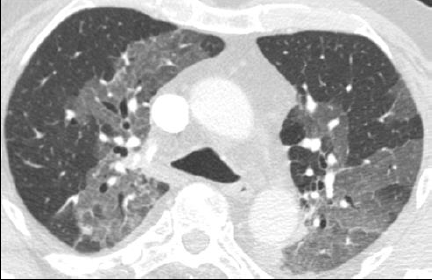

Verre dépoli